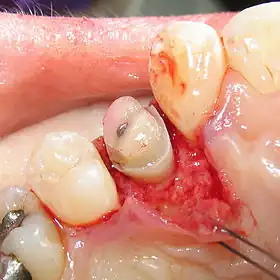

Crown lengthening is a surgical procedure performed by a dentist, or more frequently a periodontist, where more tooth is exposed by removing some of the gingival margin (gum) and supporting bone.[1] Crown lengthening can also be achieved orthodontically (using braces) by extruding the tooth.

Crown lengthening is done for functional and/or esthetic reasons. Functionally, crown lengthening is used to: 1) increase retention and resistance when placing a fabricated dental crown,[2] 2) provide access to subgingival caries, 3) access accidental tooth perforations, and 4) access external root resorption. Esthetically, crown lengthening is used to alter gum and tooth proportions, such as in a gummy smile. There are a number of procedures used to achieve an increase in crown length.[3]